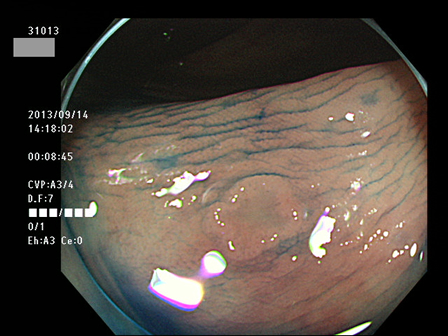

上記100名より抽出した平坦・陥凹型腺腫(=癌化の危険が高いが見落としやすい病変)の内視鏡写真